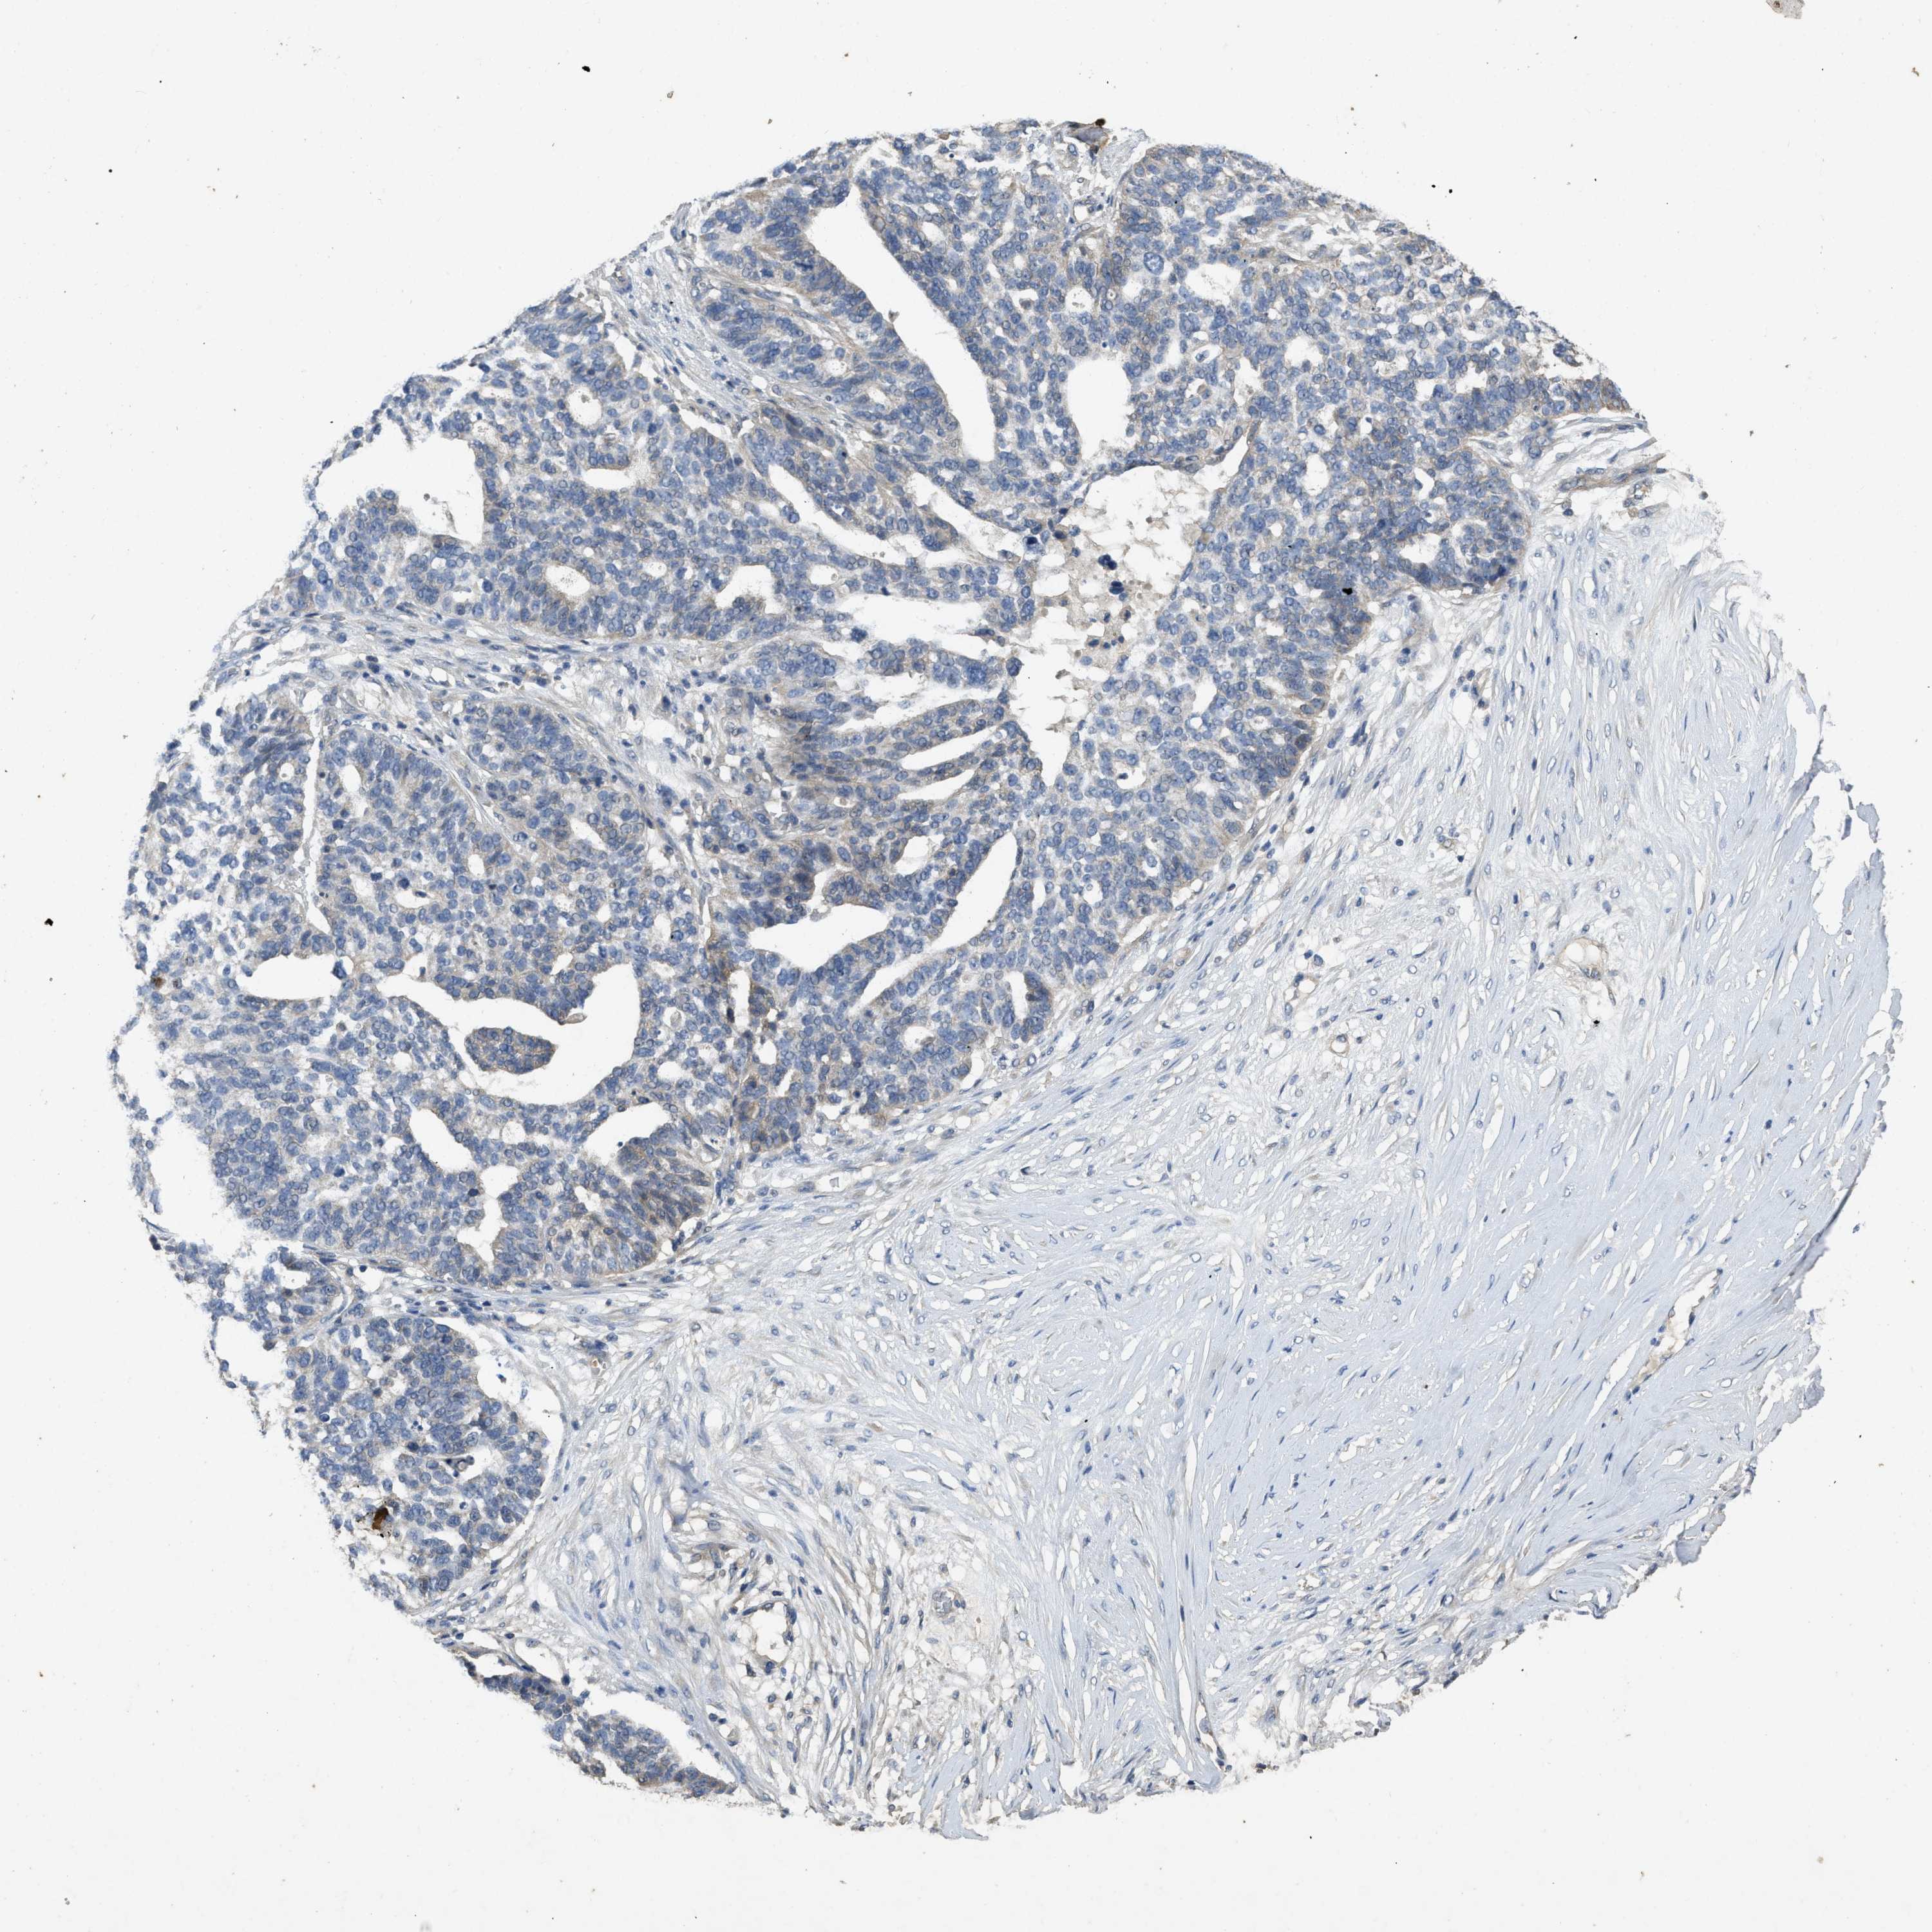

OVARIAN CANCER - Protein expressioni

A mouse-over function shows sample information and annotation data. Click on an image to view it in a full screen mode. Samples can be filtered based on level of antibody staining by selecting one or several of the following categories: high, medium, low and not detected. The assay and annotation is described here.

Note that samples used for immunohistochemistry by the Human Protein Atlas do not correspond to samples in the TCGA dataset.

Antibody stainingi

Antibody staining in the annotated cell types in the current human tissue is reported as not detected, low, medium, or high, based on conventional immunohistochemistry profiling in selected tissues. This score is based on the combination of the staining intensity and fraction of stained cells.

Each image is clickable and will lead to virtual microscopy that enables deeper exploration of all samples and also displays staining intensity scores, fraction scores and subcellular localization as well as patient and tissue information for each sample.

Antibody HPA012778

Antibody CAB018581

Staining

High

Medium

Low

Not detected

Intensity

Strong

Moderate

Weak

Negative

Quantity

>75%

75%-25%

<25%

None

Location

Nuclear

Cytoplasmic/membranous

Cytoplasmic/membranous,nuclear

Cystadenocarcinoma, serous, NOS

Carcinoma, endometroid

Cystadenocarcinoma, mucinous, NOS

Carcinoma, NOS